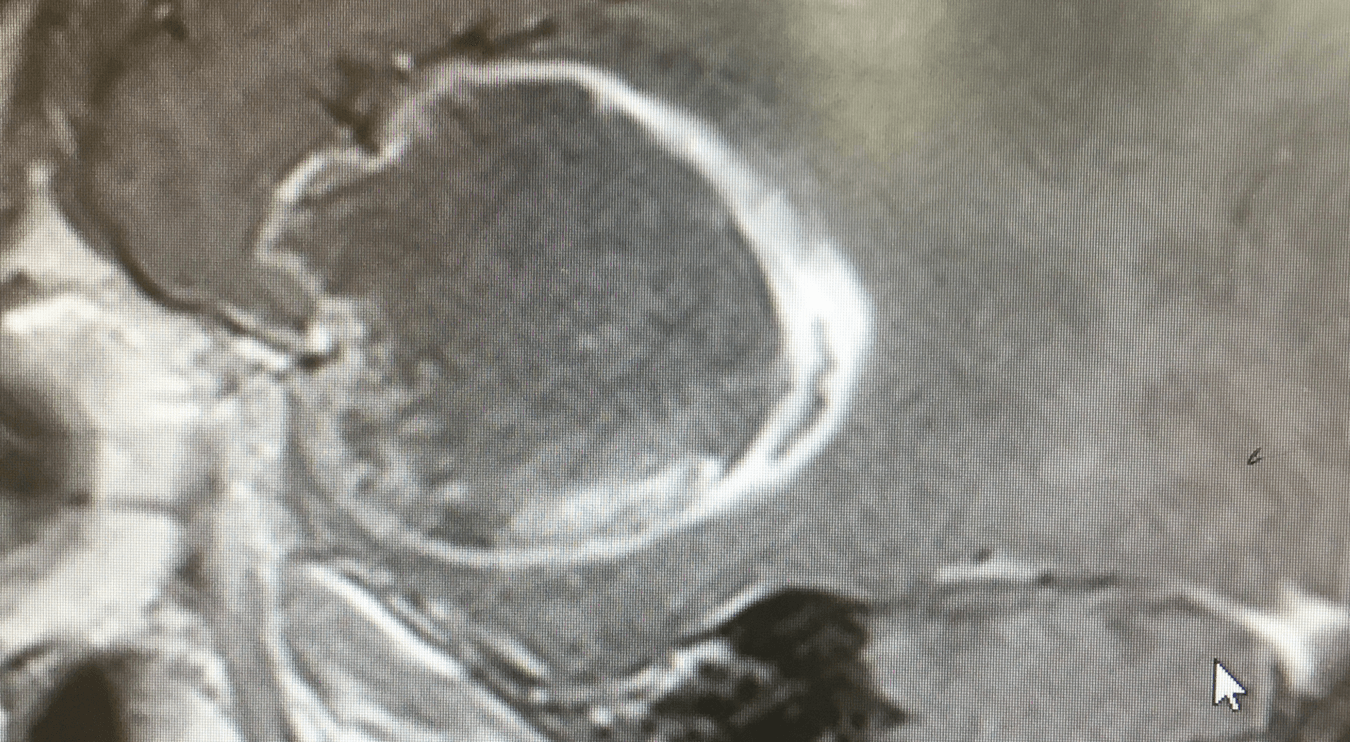

Προεγχειρητική εικόνα ασθενούς 54 ετών με γλοιοβλάστωμα WHO IV δεξιά κροταφικά και έντονα πιεστικά φαινόμενα με μετατόπιση μέσης γραμμής.